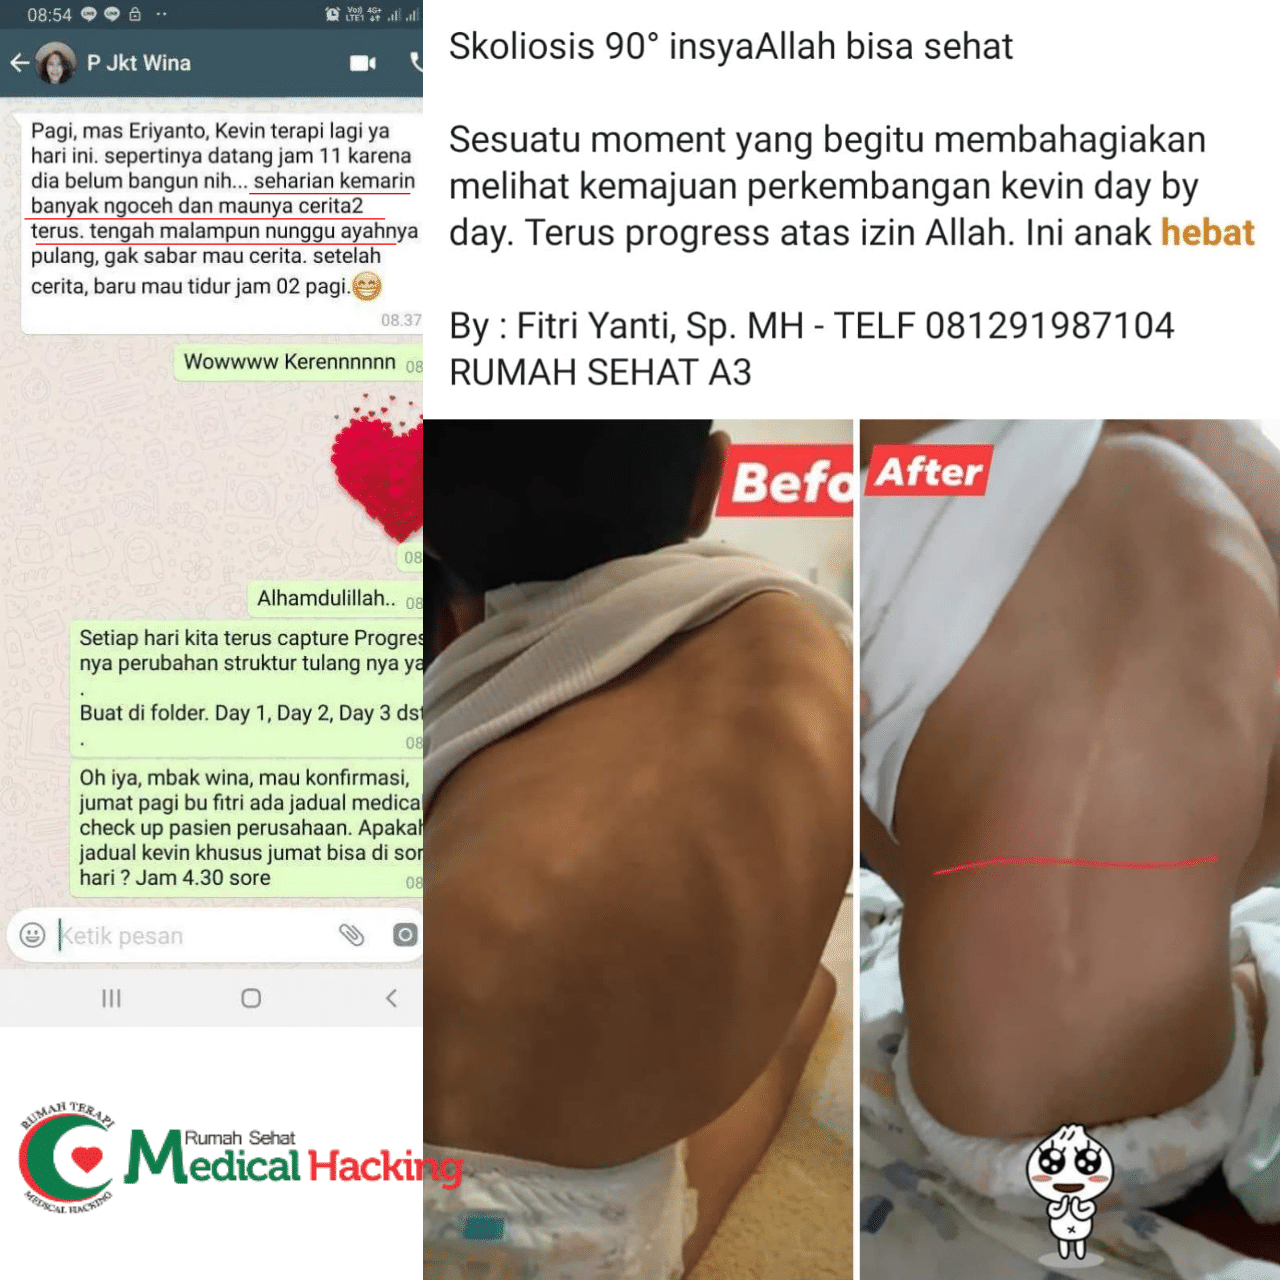

Alignment Postural: Buat benerin tulang belakang. Ini bisa bantu sistem saraf dan aliran darah ke otak biar seimbang, soalnya bagian depan otak itu ngatur perilaku.